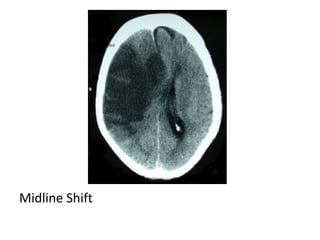

b) Generalized Mass Effect :

-Ventricular or basal cistern effacement +/-

midline shift (subfalcine herniation) or other

herniation syndromes : uncal , transtentorial

Midline Shift

CT , Hemorrhagic evolution of initial ischemic infarction with

significant midline shift